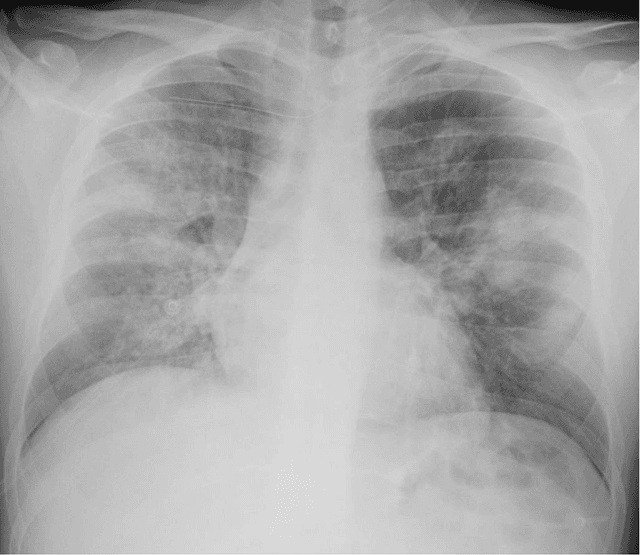

Abstract:Purpose: This study aimed to develop and validate computer-aided diagnosis (CXDx) system for classification between COVID-19 pneumonia, non-COVID-19 pneumonia, and the healthy on chest X-ray (CXR) images. Materials and Methods: From two public datasets, 1248 CXR images were obtained, which included 215, 533, and 500 CXR images of COVID-19 pneumonia patients, non-COVID-19 pneumonia patients, and the healthy samples. The proposed CADx system utilized VGG16 as a pre-trained model and combination of conventional method and mixup as data augmentation methods. Other types of pre-trained models were compared with the VGG16-based model. Single type or no data augmentation methods were also evaluated. Splitting of training/validation/test sets was used when building and evaluating the CADx system. Three-category accuracy was evaluated for test set with 125 CXR images. Results: The three-category accuracy of the CAD system was 83.6% between COVID-19 pneumonia, non-COVID-19 pneumonia, and the healthy. Sensitivity for COVID-19 pneumonia was more than 90%. The combination of conventional method and mixup was more useful than single type or no data augmentation method. Conclusion: This study was able to create an accurate CADx system for the 3-category classification. Source code of our CADx system is available as open source for COVID-19 research.